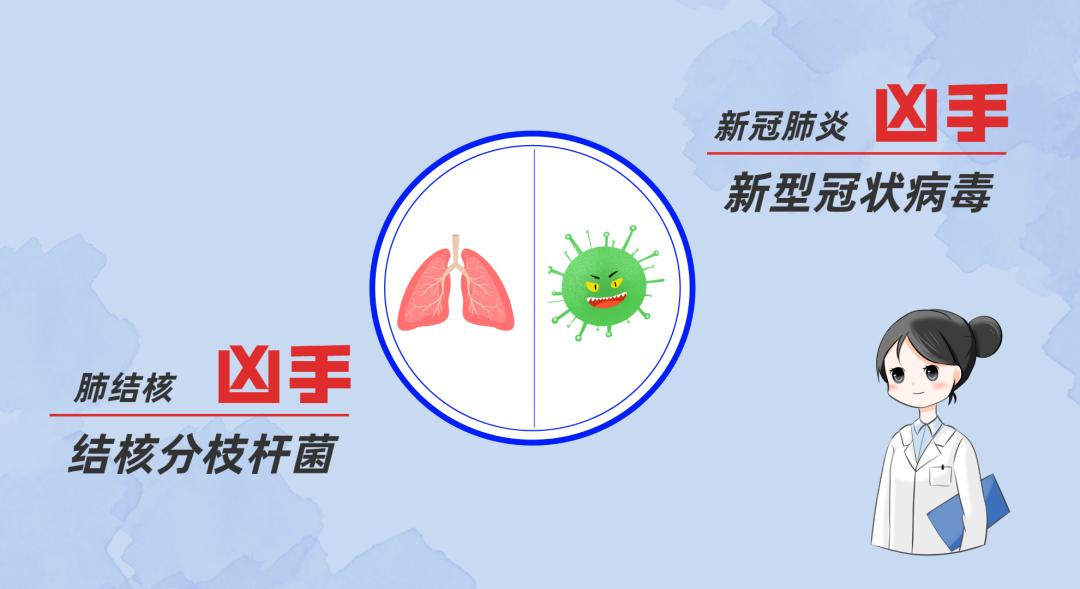

什么是结核病?

结核病是由结核杆菌感染引起的慢性传染病。结核菌可能侵入人体全身各种器官,但主要侵犯肺脏,称为肺结核病。

结核病是青年人容易发生的一种慢性和缓发的传染病。一年四季都可以发病,15岁到35岁的青少年是结核病的高发峰年龄。潜伏期4~8周。其中80%发生在肺部,其他部位(颈淋巴、脑膜、腹膜、肠、皮肤、骨骼)也可继发感染。人与人之间呼吸道传播是本病传染的主要方式。传染源是接触排菌的肺结核患者。随着环境污染和艾滋病的传播,结核病发病率越发强烈。除少数发病急促外,临床上多呈慢性过程。常有低热、乏力等全身症状和咳嗽、咯血等呼吸系统表现。

肺结核是怎么传播的?

1.肺结核是呼吸道传染病,容易发生传播。

2.结核菌通过肺结核病人咳嗽、咳痰、打喷嚏播散到空气中,健康人吸入带有结核菌的飞沫即可能受到感染。